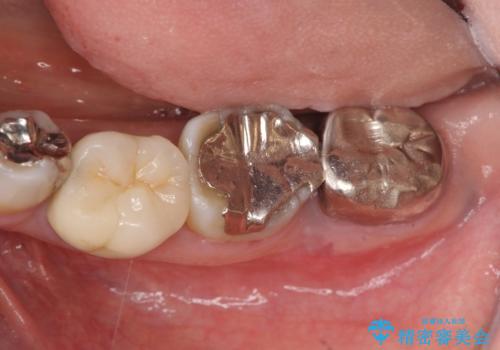

今後の機能回復方法としてインプラント治療を希望されたため、将来的に大規模な骨造成が必要とならないよう歯槽堤保存術を抜歯と同時に行いました。

- 50万円(ストローマンインプラント・骨造成・チタンカスタムアバットメント・メタルボンド)費用は治療当時の料金となります

術前、歯の破折により大きな骨の吸収が認められていたため骨量を十分に回復するために抜歯と同時に歯槽堤保存術を行い十分な骨量の回復をすることができました。